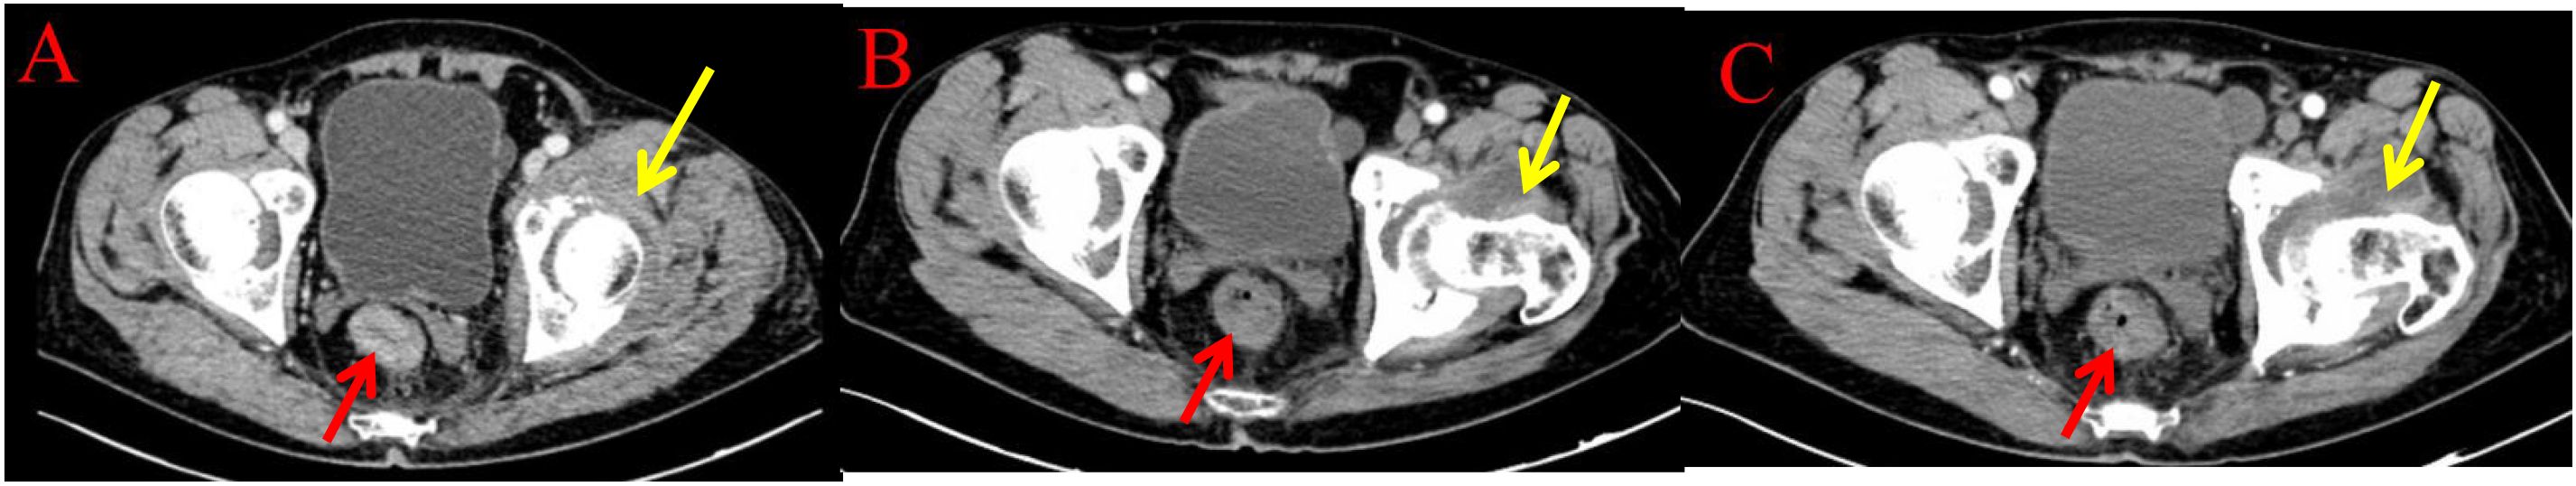

Endoscopic Examination is shown in Figure 2. Pathological Examination is shown in Figure 1. Imaging examinations of the changes in lung, gastric, intestinal and bone lesions are shown in Figures 3–5. The timeline of the diagnosis and treatment process is shown in Figure 6.

Figure 5. Imaging examinations of the changes in intestinal and bone lesions: (A) (2024.4.18) The rectal wall is locally thickened, and the enhanced examination shows mild enhancement, with a thickness of about 15mm and a cumulative length of about 46mm. The outer wall is slightly rough. Left acetabular bone resorption and destruction, accompanied by the formation of a soft tissue mass shadow. (B) (2024.12.10) The rectal wall is locally thickened, and the enhanced examination shows mild enhancement. The intestinal lumen is narrowed, and the outer wall is slightly rough. Left acetabular bone resorption and destruction, accompanied by the formation of a soft tissue mass shadow. (C) (2025.3.26) The rectal wall is locally thickened, and the enhanced examination shows mild enhancement. The intestinal lumen is narrowed, and the outer wall is slightly rough. Left acetabular bone resorption and destruction, accompanied by the formation of a soft tissue mass shadow.